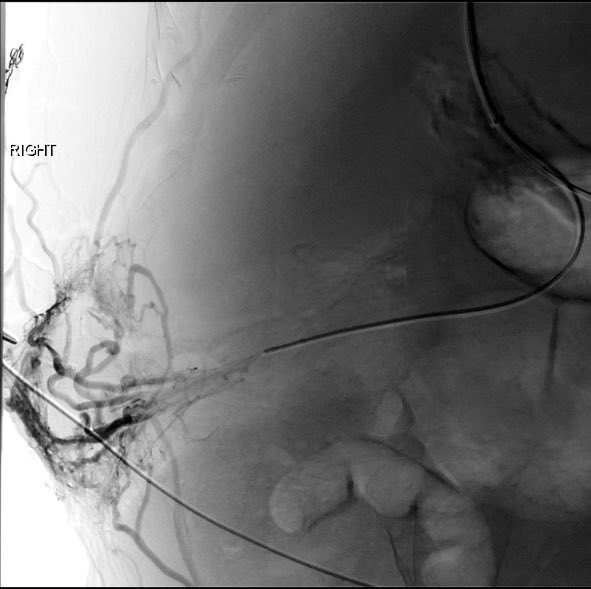

The day continued with a post renal biopsy bleed with active extravasation and a pseudoaneurysm, both of which were easily addressed with LAVA-18. Both patients are doing well after successful procedures. @SirtexMedical @thegestgroup

First day with LAVA-18 and it was quite the day. Our first case was a hypotensive patient with a pelvic fracture and active bleeding (with the LAVA coming off the delivery truck right to the angio suite and right into the patient). @SirtexMedical @thegestgroup